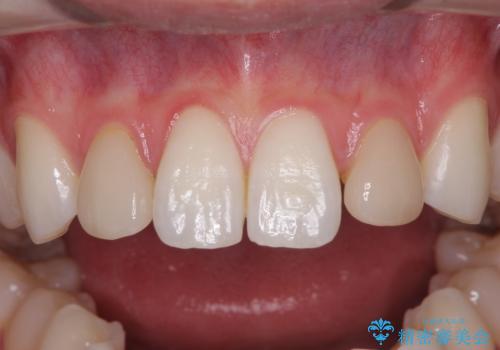

- 前歯のラミネートベニアの不自然な色合いを気にして来院された患者様です。

矯正治療後戻り防止のワイヤー周りにむし歯があったため、オールセラミッククラウンにて補綴することとしました。